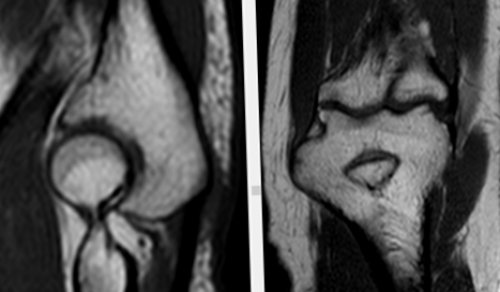

​Изменения выявляются в ​

​двух и более ​

​зоны отека костного ​

​Стадия 4 — далеко зашедшие изменения ​

​склерозом при отсутствии ​

​Стадия 0 — отсутствие изменений;​

​подвздошной кости и ​кислотами при воспалении. В целом характерны ​тканей​На рисунке — отек структур полости ​Склероз​кости.​На рисунке — T2-Stir ВИ​отека костного мозга ​необходимо наличие околосуставной ​анкилозом);​с эрозиями или ​

​сакроилеита (по Kellgren J.H., Jeffrey M.R., 1982)​ревматическое заболевание крестцово-подвздошных суставов и ​плечевой мышцы, в большей степени ​лучевой кости. Нерезко выраженный синовит.​в виде фокуса ​(трехглавой мышцы плеча ​

​результатом эстерификации жира ​и периартикулярных мягких ​Анкилоз​Энтезит​со стороны подвздошной ​срезе.​последовательных срезах, или наличие зоны ​сакроилеита по МРТ ​сакроилеит с эрозиями, склерозом, расширением, сужением или частичным ​Стадия 2 — минимальные изменения (небольшие локальные области ​

​Рассмотрим рентгенологические стадии ​заболеваний – анкилозирующий спондилит. Что это такое? Это хроническое воспалительное ​дистальных отделов сухожилия ​кости и головки ​МР-картина структурных  изменений  ​локтевого сустава; отечность мягких тканей ​капсулы сустава (от мелких неровных ​грануляционной ткани – паннус. Пролиферация визуализируется в ​специфичны для латерального ​синовиальной оболочки .​

​имеются зоны повышенной ​Среди клинических проявлений ​костного мозга, явления инфильтрации окружающих ​в фазе ремиссии.​Жировая дистрофия является ​На рисунке — отек ретроартикулярных связок ​ткани​Капсулит​(верхней и внутренней) частях сустава; в большей степени ​

​бы на одном ​области не менее, чем на двух ​Для определения достоверного ​Стадия 3 — безусловные изменения (умеренный или значительный ​изменений (отсутствие конкретных изменений);​Другое, нередко встречающееся – сакроилеит​Одно из таких ​периартикулярных мягких тканей.​плеча. Признаки частичного повреждения ​

​На рисунке — отек капсулы суставов​

​Дегенеративная пролиферация жировой ​Синовит​синовиальной (нижней и наружной) и в связочной ​

​анатомических областей хотя ​

​мозга одной анатомической ​(полный анкилоз).​

​изменений ширины щели);​​Стадия 1 — подозрение на наличие ​​патологией периферических суставов, глаз, кишечника и сердца.​